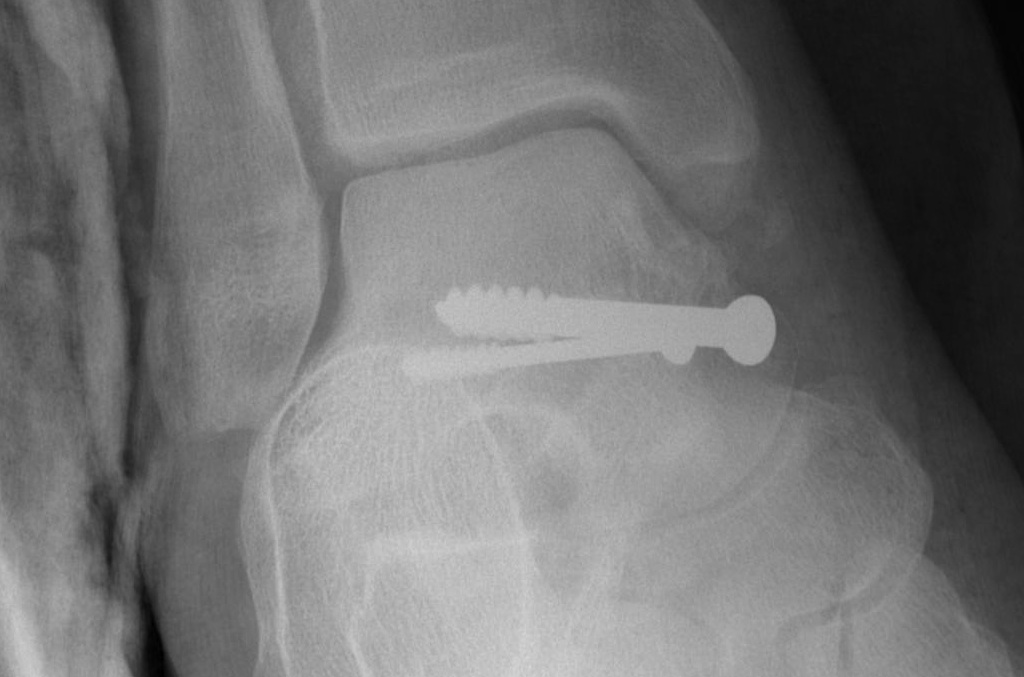

Cannulated screws

Xrays

| AP | Lateral | Canale View |

|---|---|---|

| Entry point of the screws |

Evaluate neck reduction

|

Evaluates the neck reduction |

Lateral off articular surface Medial through articular cartilage |

Depth of screws |

Beam angled 75o to foot Foot 15o pronated |

1. Retrograde (anterior to posterior) into posterior talus body

A. Lateral screw

- insert proximal to articular surface of head on lateral side

- bone is very curved here

- can lag screw as usually no comminution

B. Medial side

- insert through articular surface

- countersunk screws through articular surface

- avoid lag screw techniques medially as may compress comminution into varus

AP, Canale and Lateral xray

Retrograde screws